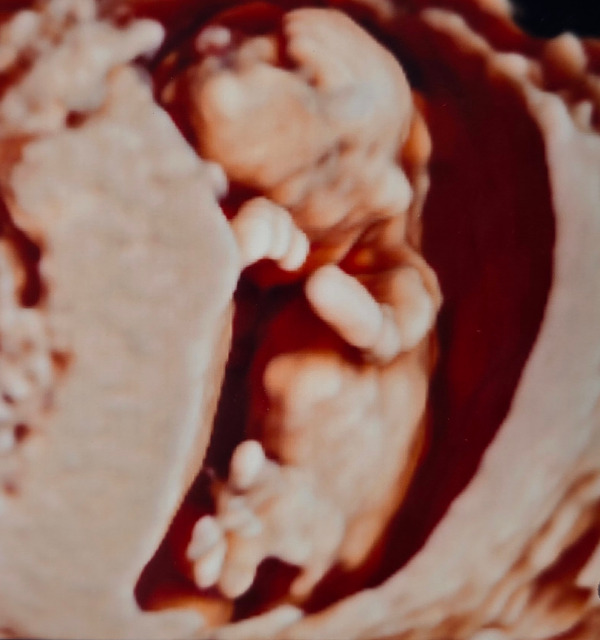

임신 중반을 지나면서 아내의 배가 점점 불러왔다. 여전히 입덧이 있었지만 초기보다는 많이 나아져서 먹을 수 있는 음식도 많이 늘어났다. 계속 줄어들기만 하던 몸무게도 양수와 둥글이의 영향인지 다시 늘기 시작했다. 27주 차에 두 번째 입체초음파 검사를 하였다. 입체 초음파 검사는 일반 초음파와 달리 아이의 형상을 3D 입체 영상으로 확인할 수 있는 검사다. 이미 12주 차 첫 번째 입체초음파 검사를 했었는데, 이때는 둥글이의 머리통과 팔다리 형상만 겨우 구분할 수 있었다. 그런데 두 번째 입체초음파 검사는 달랐다. 우리 부부는 이날 둥글이의 얼굴을 처음으로 선명하게 보았다.

1-10.jpg

1-11.jpg

12주 차와 27주 차의 입체 초음파 사진. 한 화면에 들어오지 않을 만큼 컸다.

어느새 쑥쑥 자라 한 화면에 담을 수도 없는 둥글이는 슬며시 얼굴 반쪽을 내보여 주었다. 감고 있는 눈과 작은 코, 심통 난 듯 불퉁한 볼과 입까지... 마치 아이를 눈앞에 두고 있는 듯 생생한 모습이었다.